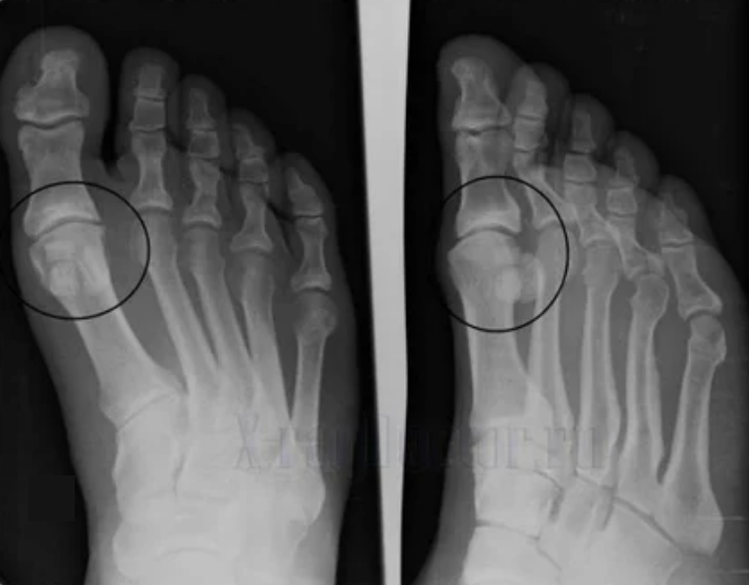

- Reduce the gap into the gap of the joint, which becomes evident in the photo.The stage of the violation is determined by the diagnostic-anthgenologist.The patient feels the complexity or inability to straighten and completely fold the limb;

To make a diagnosis, rheumatologists study the patient's complaints and prescribe an X -ray exam. Very often, radiography is used in 2 projections.The doctor examines the presence of dystrophic disorders in the Ialina cartilage and in the bone joints.If the joint gap is reduced, the bones are deformed or flattened, there are cystic formations on the surface of the cartilage, osteophytes are evident signs of arthrosis.During the inspection, arthrosis indicates the instability of the joint: the axis of the limbs and the subluxation is disturbed.

Often a X -ray image is not able to provide complete information on the condition of the joint.For a more in -depth study, computerized tomography is prescribed, it is effective for examining the bones.Magnetic resonance imaging is most often used to study soft tissues.